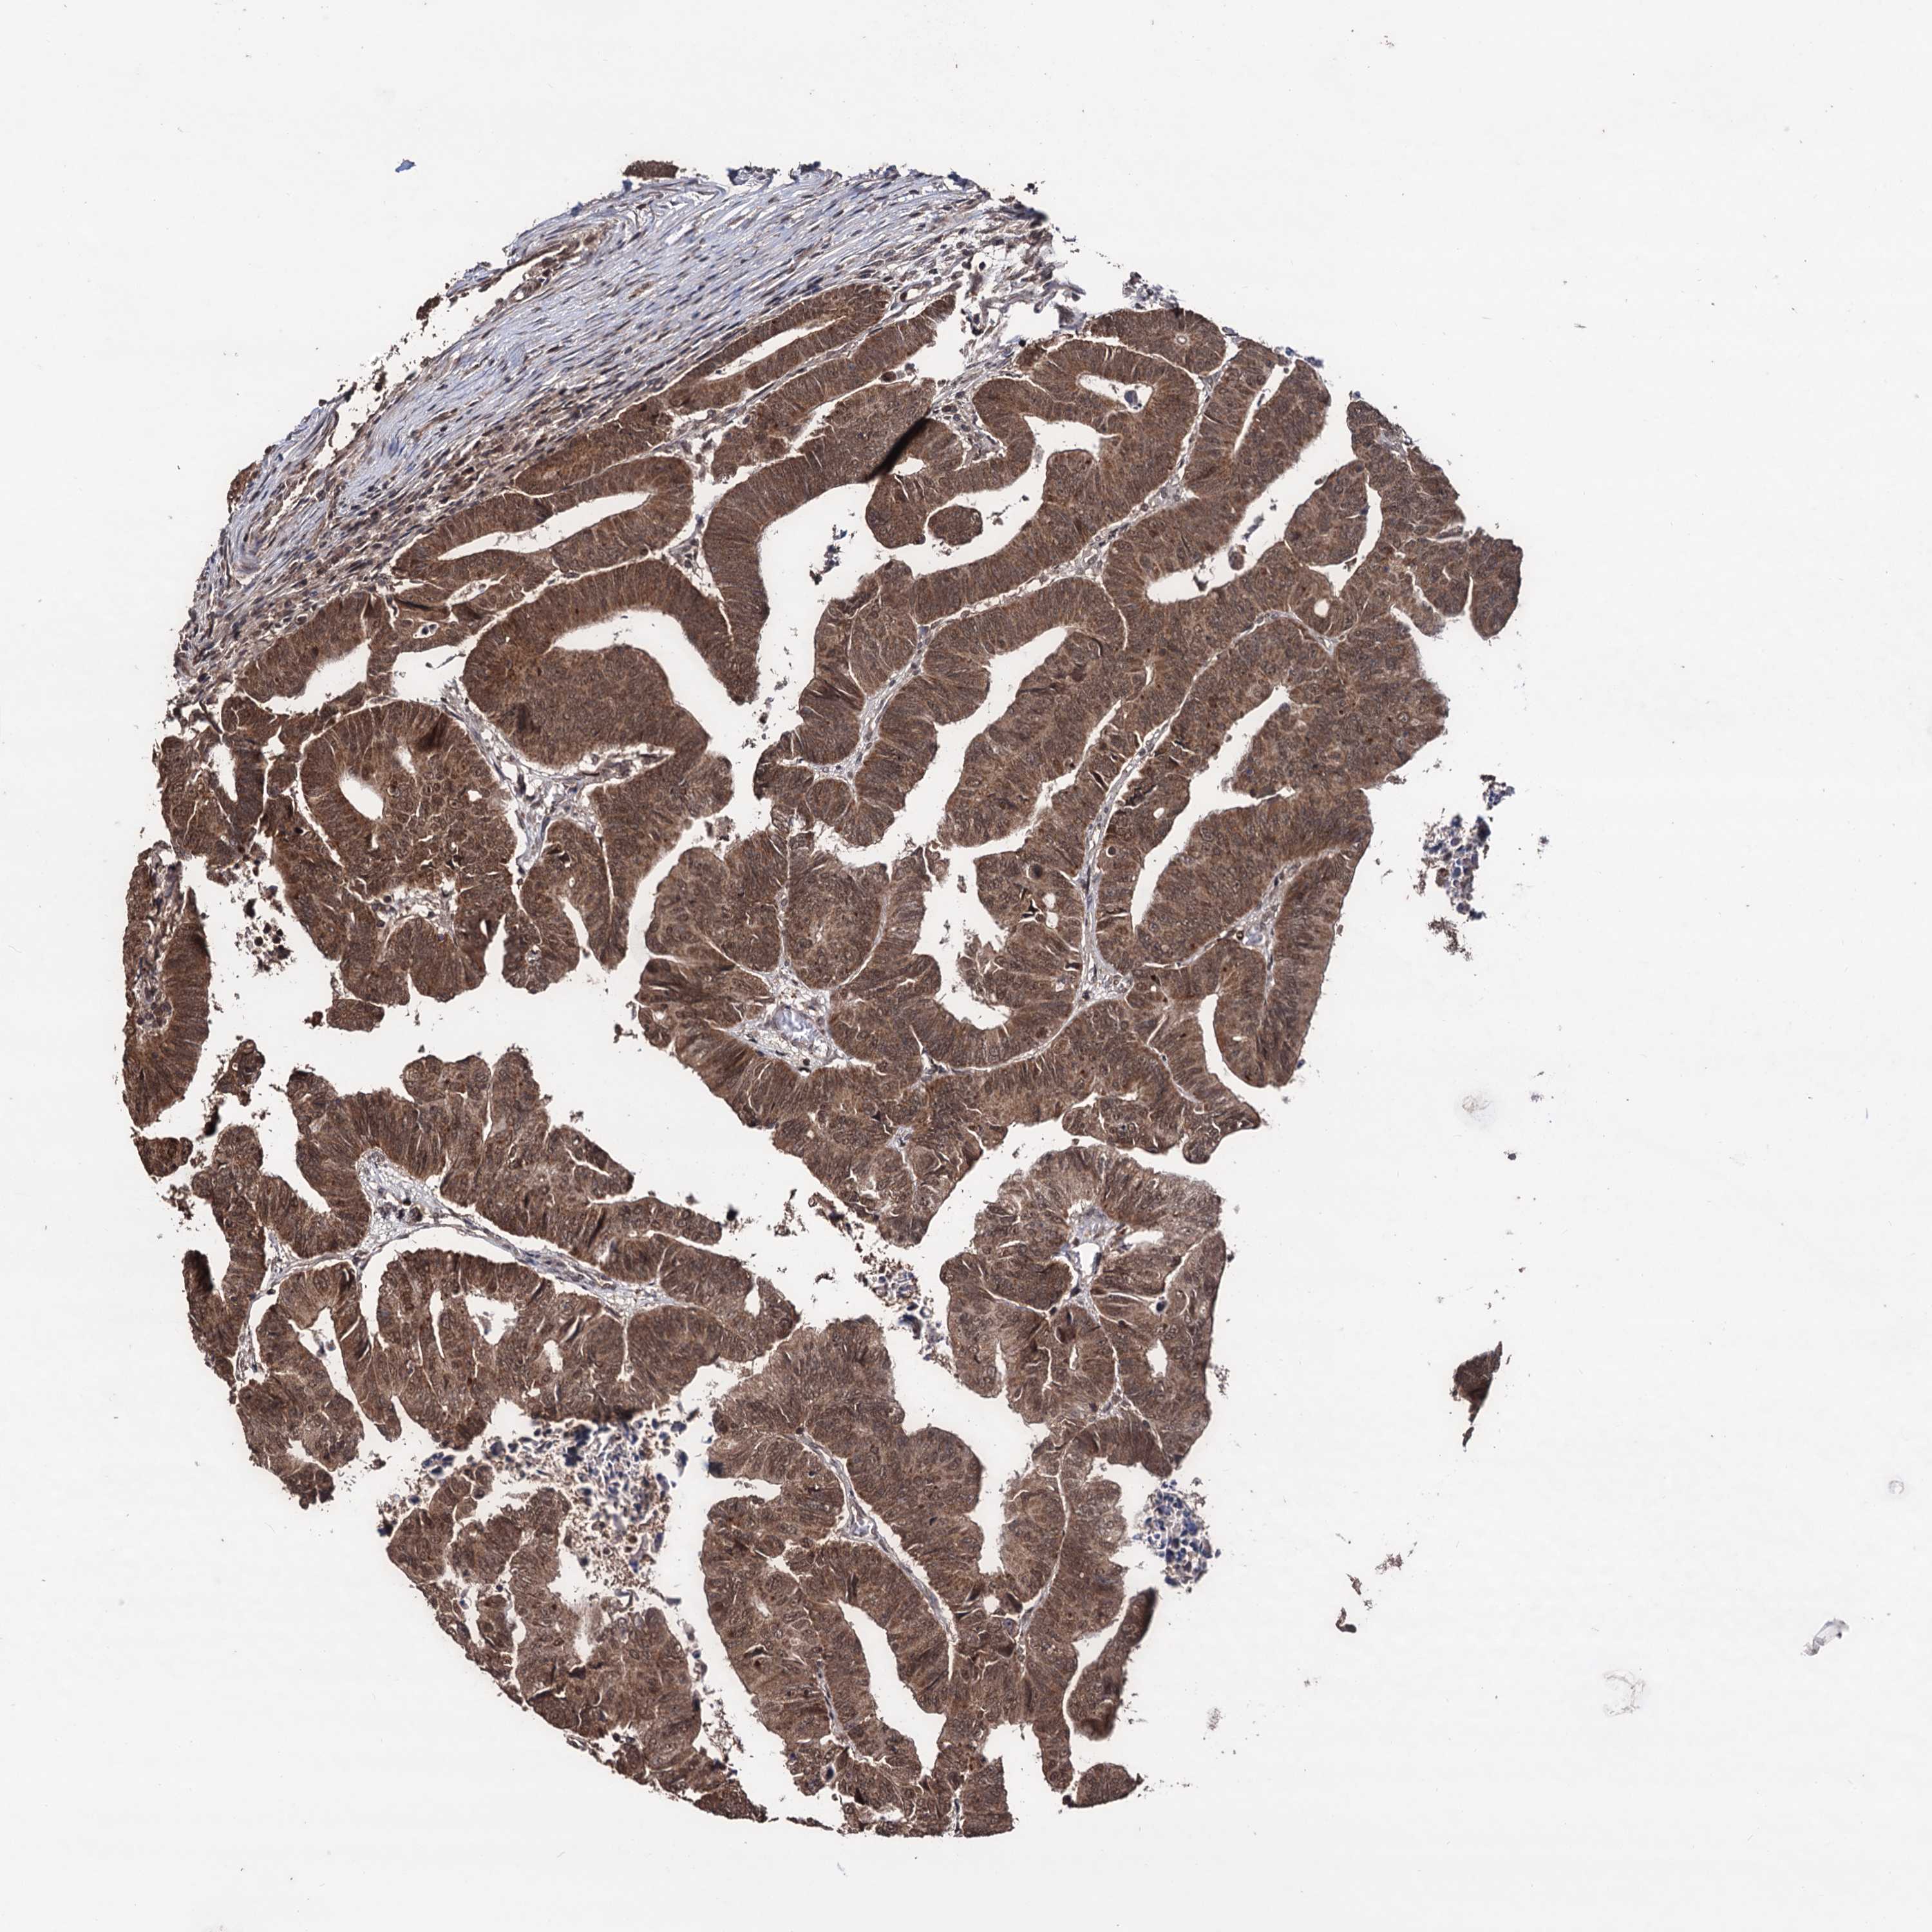

CANCER COLORECTAL CANCER Show tissue menu

Colorectal cancer

Human cancer

Colon adenocarcinoma